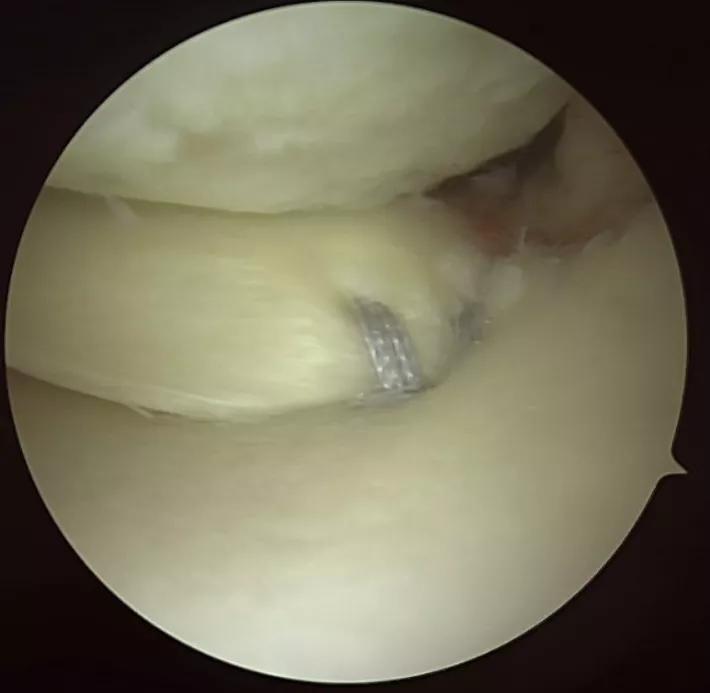

A torn meniscal root with sutures

Repairing a torn meniscal root

A. Coronal MRI image demonstrating root tear (arrow); B. Medial meniscus root tear (triple arrow); C. Sutures placed into the root prior to reduction and fixation of the root; D. Root sutures tensioned and meniscus root repaired to footprint.